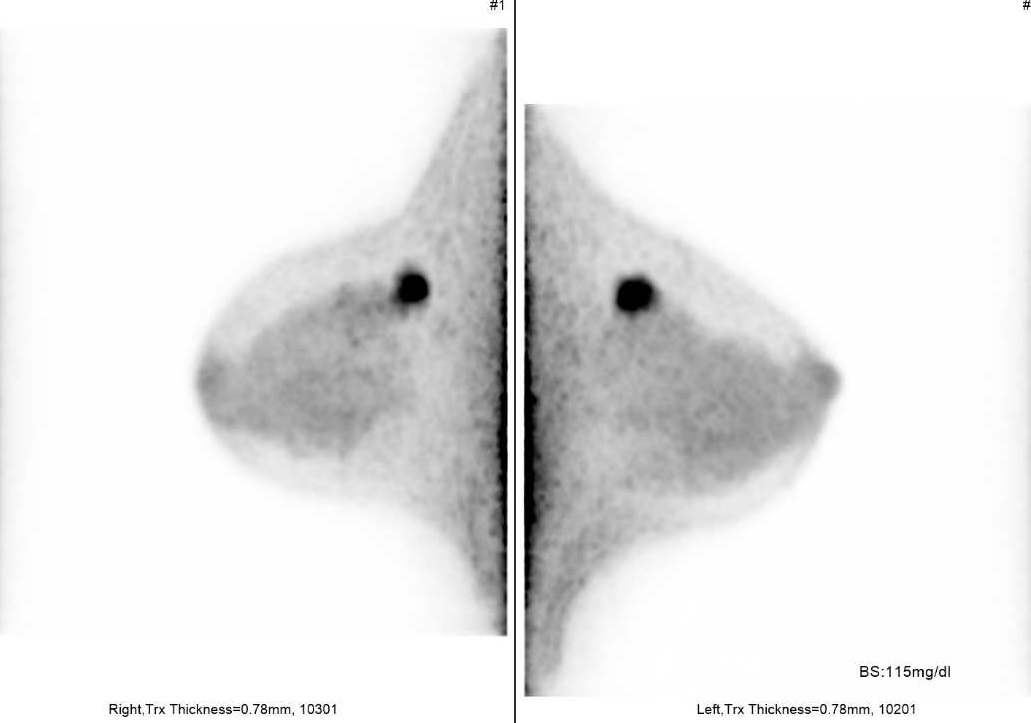

乳房専用PET検査画像(両側乳がん)